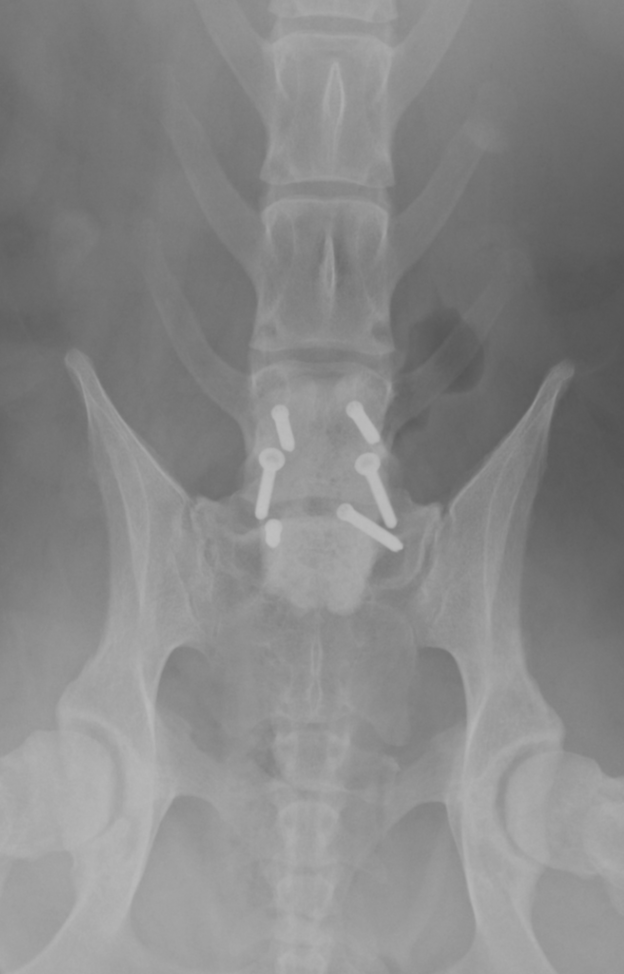

斜めに入っているスクリュー2本が経関節固定のスクリューで、他の4本は骨セメント固定用のスクリューです。

真ん中の2つが経関節固定のスクリューで、前後2本ずつ入っているのが骨セメント用スクリューです。

それを覆う四角形のものが骨セメントです。

スクリューにはロッキングスクリューを利用しています。